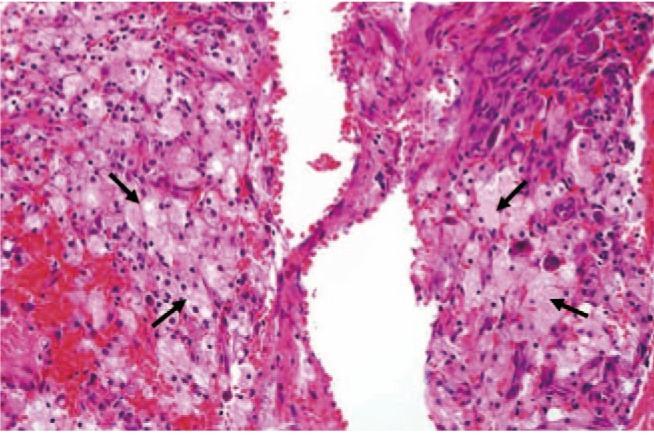

We report the case of a 25-year-old woman presenting with left hip pain. A lesion was found in the proximal femoral metaphysis. Benign bone tumor, such as intraosseous lipoma or liposclerosing myxofibrous tumor, was suspected based on simple radiographs and magnetic resonance images. Curettage of the lesion and bone grafting was performed. Histologic findings reflected primary intraosseous xanthoma of the proximal femur. Laboratory tests revealed the patient to be normolipidemic, while immunoelectrophoretic fractionation of lipoproteins revealed normal values for alpha, pre-beta, beta, and chylomicrons. At the one-year follow-up, there was no evidence of local recurrence. This is the first reported case of primary intraosseous xanthoma of the proximal femur in a normolipidemic patient.

我们报告了一例25岁女性因左髋部疼痛就诊的病例。在股骨近端干骺端发现一个病灶。基于普通X线片和磁共振成像,怀疑为良性骨肿瘤,如骨内脂肪瘤或脂肪硬化性黏液纤维瘤。对病灶进行了刮除和植骨。组织学检查结果显示为股骨近端原发性骨内黄瘤。实验室检查显示患者血脂正常,而脂蛋白免疫电泳分离显示α、前β、β和乳糜微粒值正常。在一年的随访中,没有局部复发的迹象。这是首例血脂正常患者的股骨近端原发性骨内黄瘤报告病例。